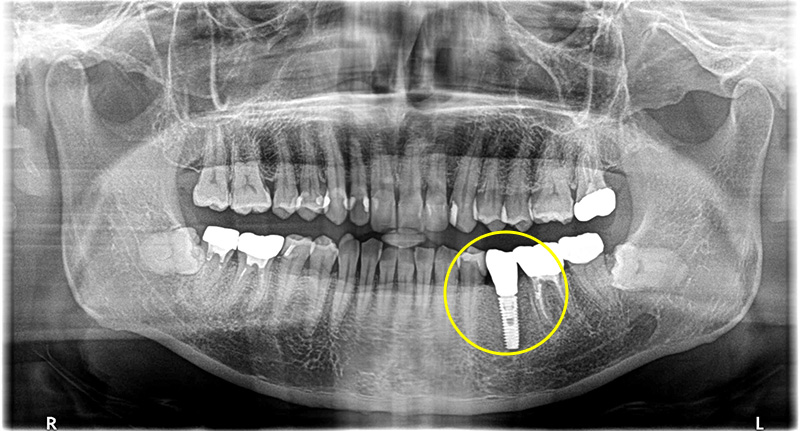

根っこが膿んでいる歯を抜歯してインプラントで修復した症例

こちらの患者さまは、左下前から5番目の歯が噛むと痛いとの主訴で来院されました。

CT検査の結果、過去に他院で治療した歯の根っこが膿んでいることがわかりました。

一度被せ物を除去し、中身の状態を確認したところ、歯の根っこに破折線が見られたため、患者様のご希望で、抜歯、インプラントを行うことになりました。

歯が破折していることにより、膿が大きく骨欠損が多かったため、インプラントの持ちを良くするために骨造成も同時に行っています。